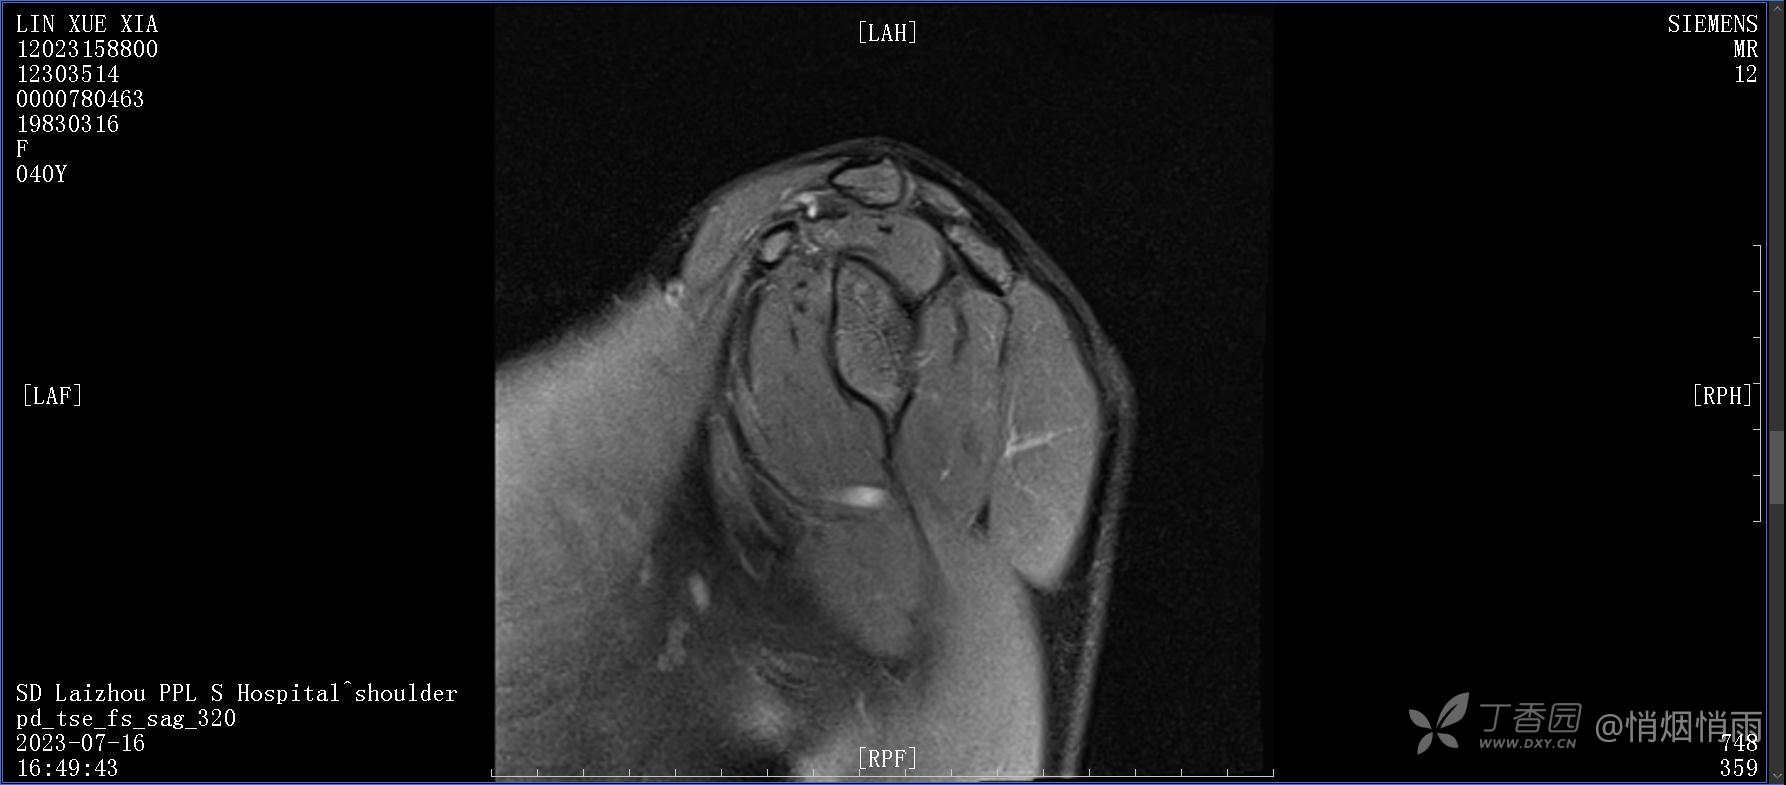

查体:右肩关节局部轻度肿胀,肩胛区压痛明显,痛处不固定,肩关节痛性活动受限,jobe test(+),lift -off test(+),中指、环指感觉较余指减退,余肢端感觉及血运情况可。

目前的诊断,暂时依据辅助检查诊为肩袖损伤,但是患者疼痛的性质和特点,却不是单纯的肩袖损伤所致。考虑过胸廓出口综合征,但是该疾病会出现肩胛区的疼痛吗?(由于考虑到费用的问题,没再进行下一步的检查)带状疱疹会有如此的症状吗?